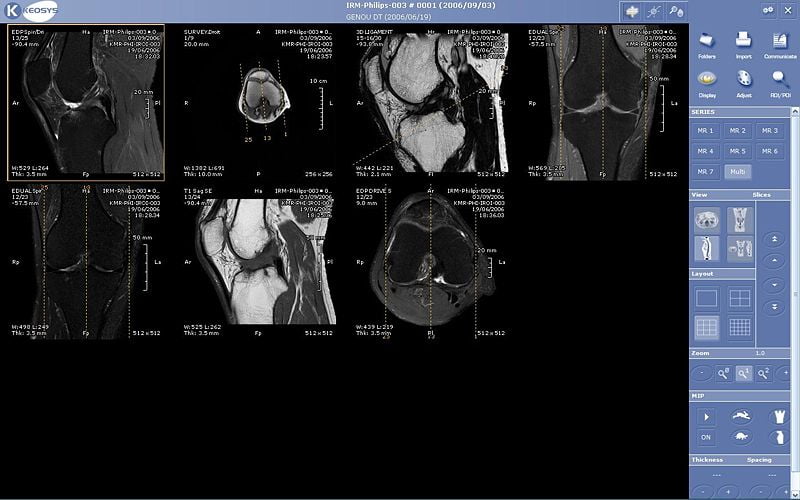

Este artículo es el tercero de la “mini-serie de las tomografías” dedicada a la Tomografía por Emisión de Positrones (TEP), [Tomografía Axial Computarizada (TAC)](https://eltamiz.com/2008/01/22/¿en-que-consiste-una-tomografia-axial-computarizada-tac/ “”), la Resonancia Magnética Nuclear (RMN), Imagen por Resonancia Magnética Nuclear (IRMN) o Tomografía por Resonancia Magnética (TRM) y, en un mes o dos, la ecografía. Como hicimos en los otros dos casos, hablaremos sobre los fundamentos físicos en los que se basa, cómo funciona técnicamente, para qué sirve y qué peligros entraña. Ojito a la secuencia de “rodajas” de una cabeza humana, que es algo grimosa pero fascinante. Yo juraría que es de Homer Simpson:

Esto significa que, en el ejemplo anterior, la frecuencia de Larmor de los protones de tu espalda es menor que la de los del pecho, y que en definitiva tu cuerpo estaría “cortado en rodajas” de un grosor muy pequeño, de protones girando con una frecuencia, justo encima otra “rodaja” de protones girando un poquito más rápido, etc. Pero ¿cómo distinguir unas “rodajas” de otras?

Aunque el proceso es bastante complicado y requiere el análisis de Fourier de las ondas recibidas, creo que puede entenderse el mecanismo básico por el que se forma la imagen de la rodaja: los dos planos perpendiculares a la rodaja son controlados por los campos gradientes, que son capaces de “cortar” seleccionando frecuencias de Larmor e ir seleccionando cada fila y columna, de modo que las bobinas receptoras son capaces de identificar de dónde proviene cada pulso de energía radiante.

Ah, pero no todas las peonzas de tu cuerpo tardan lo mismo en volver a su posición inicial; no todas las mini-cuerdas de guitarra dejan de sonar igual de rápido. La razón es que el número de protones en los diferentes tejidos de tu cuerpo no es el mismo: unas partes son más densas que otras, y unas moléculas (como el agua) tienen un número de protones diferentes del de otras (como una proteína). Estos tiempos son similares (del orden de magnitud de un segundo), pero no idénticos. Si “coloreas” de un color determinado los puntos en los que un porcentaje fijo de núcleos atómicos vuelven a su posición inicial en menos de cierto tiempo, de un color diferente los que tardan un poco más, etc. (por ejemplo, de negro a blanco según aumenta el tiempo), tienes un mapa de tejidos del cuerpo en la “rodaja” que has elegido.

Una ventaja de la RMN es que modificando continuamente los imanes secundarios pueden obtenerse imágenes consecutivas (naturalmente, no con una enorme resolución) de una “rodaja” determinada, de modo que lo que se tiene entonces es una especie de película en la que los tejidos blandos y los fluidos corporales se distinguen con gran claridad. No te pierdas esta secuencia de un corazón latiendo… ver el flujo de la sangre me parece impresionante: